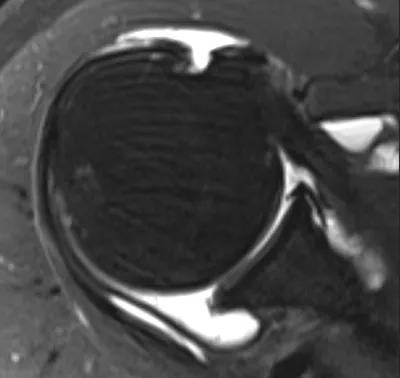

SLAP tear (Superior Labrum Anterior and Posterior)

Arthrogram

4/11/2026